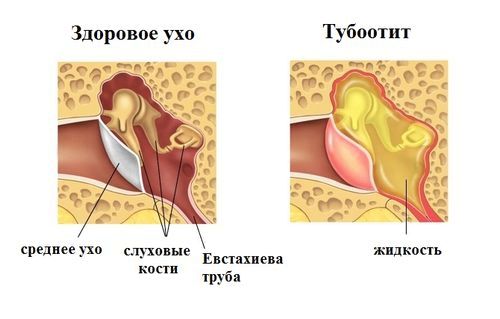

Тубоотит (євстахіїт) - це захворювання, що провокує запалення слизової оболонки євстахієвої трубки, яке призводить до її набряклості і звуження.

Запалення, утворене в ході евстахиита, може стати причинному потовщення слухової труби і зниження тиску всередині вуха. Наведені симптоми можуть привести до западання барабанної перетинки у внутрішнє порожнину вуха.

Даний стан провокує відчуття закладеності. Паралельно з наведеної симптоматикою розвивається злипання слухової труби - стенозирование. Якщо нехтувати лікуванням даних ознак евстахиита, то це може спровокувати розвиток таких ускладнень як глухота і приглухуватість.

- відчуття наявності рідини в вусі.